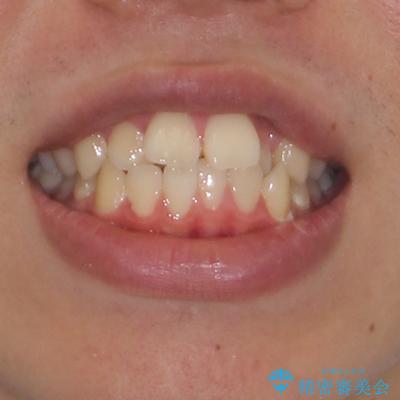

- 前歯のデコボコと口元の突出感を気にして来院された患者様です。

上下前歯がくちばしのように突出していたため、上下左右の第一小臼歯4本を抜歯し、ワイヤー装置にて矯正治療を行うこととしました。

上顎骨に対して下顎骨がやや前方位に位置しているため、下顎前歯をあまり内側に移動させることができず、口元の突出感改善は期待以上にはならないと予測しておりましたが、満足いくの引っ込み具合となりました。